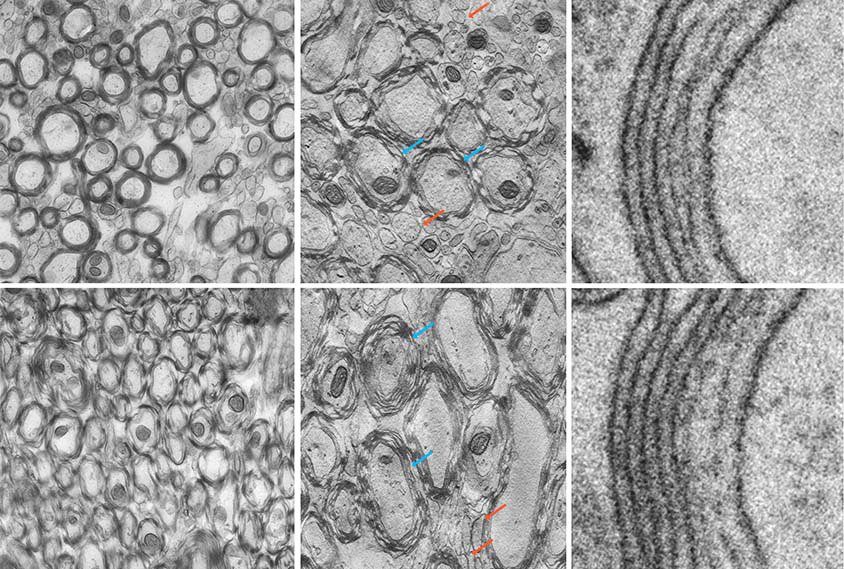

Gut molecule linked to decreased myelination in mouse brains

Targeting the molecule, 4EPS, with an experimental drug may be a way to ease anxiety for autistic people, the researchers say. But not everyone is convinced.

Gut molecule linked to decreased myelination in mouse brains

Targeting the molecule, 4EPS, with an experimental drug may be a way to ease anxiety for autistic people, the researchers say. But not everyone is convinced.